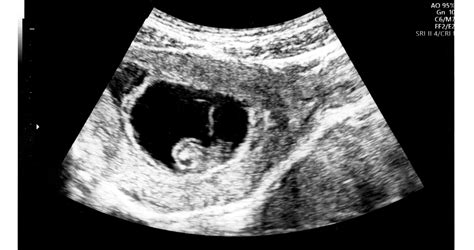

A magzati agyi ciszták felfedezése szinte kivétel nélkül a rutin terhességi ultrahang vizsgálatok során történik. Ezek a vizsgálatok kulcsfontosságúak a magzat fejlődésének nyomon követésében és az esetleges rendellenességek korai felismerésében. A legtöbb ciszta a 18-22. hét közötti genetikai ultrahang vizsgálat során válik láthatóvá.

Az ultrahang képen a ciszták jellemzően jól körülhatárolt, sötét, folyadékkal telt területekként jelennek meg. Egy tapasztalt ultrahangos szakember már az első észlelést követően képes megkülönböztetni a leggyakoribb, általában jóindulatú choroid plexus cisztákat a ritkább, potenciálisan súlyosabb elváltozásoktól.

Magzati ultrahang a második trimeszterben

A choroid plexus az agy azon része, mely nem érinti a gondolkodást, a személyiség fejlődést és egyéb agyi funkciókat sem, sokkal inkább annak a folyadéknak az előállításáért felelős, mely védi és táplálja az agyat, valamint a gerincvelőt. Abban az esetben, mikor az ultrahangon egy folyadékkal teli üreg látható a choroid plexusban, choroid plexus cisztáról (CPC) beszélünk. Függetlenül a choroid plexus ciszta méretétől, alakjától és mennyiségétől, a CPC nem tumor vagy rák, nem veszélyes a babára és a terhesség harmadik harmadára, általában a 24-26 hét között teljesen felszívódik, de az is előfordul, hogy teljesen egészséges gyermekeknél vagy felnőtteknél is kimutatható. Ha a CPC nem társul semmilyen más rendellenességgel, izolált cpc-ről beszélünk. Ha a CPC-n kívül más rendellenességet nem találnak, azaz izolált CPC-ről van szó, annak kockázata, hogy a magzatnak kromoszóma rendellenessége van, kevesebb, mint 1%. Eszerint 99%, hogy teljesen egészséges, és nincs semmiféle kromoszóma rendellenessége.